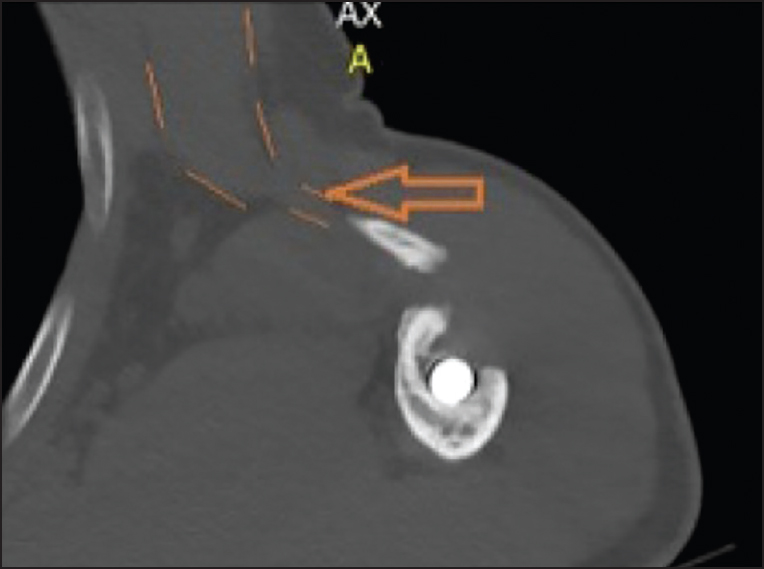

One year later, the patient still experienced pain, aggravating at night. On clinical examination, the elevation was limited to 80°, and he had a general atrophy of his left upper arm. Electromyography revealed a recovering brachial plexus injury. Constant-Murley score [2] reached only 44/100 (10/15 pain; 12/20 ADL; 22/40 mobility; and power 0/25) versus 93/100 (15/15 pain; 20/20 ADL; 40/40 mobility; and power 18/25) for the unaffected side. Besides the loss of power and limited range of motion, he experienced an induration at the anterior fold of his axilla. At the outpatient visit, 1-year after the injury, plain X-ray [Figure 3] showed a nonunion of a butterfly fragment that was displaced from its initial site. It was located in the anterior fold of the axilla. Ultrasound and CAT-scan [Figure 5] confirmed its position and showed the continuity of the fragment with the pectoralis major muscle. Due to the predominantly neurogenic pain complaints, related to the recovering brachial plexus lesion, it was decided not to repair the pectoralis major tendon avulsion and to continue physiotherapy. | Figure 5: Computed tomography scan of the nonunited fragment, confirming continuity with pectoralis major

Click here to view |